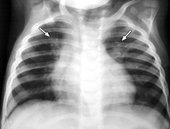

В Красноярском крае школьники массово заболели пневмонией 28.11.2013 13:52

Роспотребнадзор расследует факт групповой заболеваемости внебольничной пневмонией среди учеников Ермаковской СОШ № 1. Как сообщили в пресс-службе ведомства, в школе, расположенной в селе Ермаковское, зарегистрировано 10 случаев заболевания данной инфекцией. В целях локализации и ликвидации очага проводится комплекс противоэпидемических мероприятий. Решением санитарно-противоэпидемической комиссии Ермаковского района введены дополнительные противоэпидемические мероприятия. Постановлением главы Ермаковского района в школе с 25 ноября по 4 декабря приостановлен учебный процесс. В настоящее время дети находятся под медицинским наблюдением в МБУЗ «Ермаковская ЦРБ», угроза для жизни детей отсутствует. Новых случаев внебольничной пневмонии не выявлено.